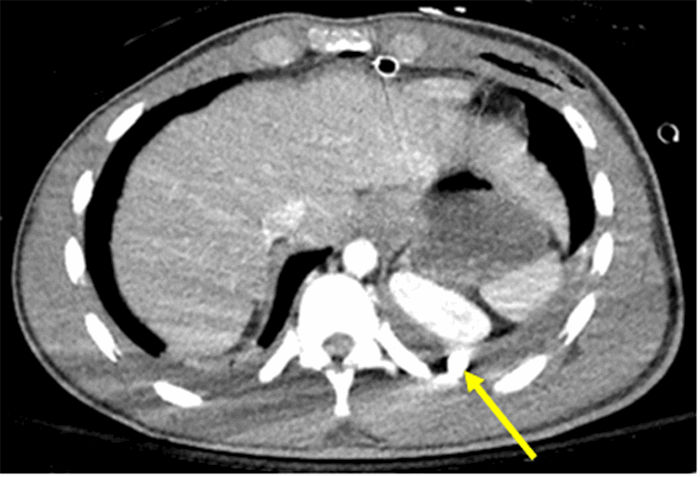

The patient was taken urgently to the operating room for further evaluation, as the CT findings did not guarantee a linear bullet trajectory across the anterior mediastinum superior to the heart and did not definitively rule out cardiac, esophageal, or tracheobronchial injuries. Despite his negative FAST exam, the patient's bilateral hemothoraces raised the possibility of an occult cardiac injury decompressing into his pleural spaces (Figure 4).

Figure 4. Axial CT image of patient with Transmediastinal gunshot wound depicting bullet location. Solid yellow line indicates the position of the bullet in the left diaphragmatic sulcus, posterior to the left kidney on CT scan.